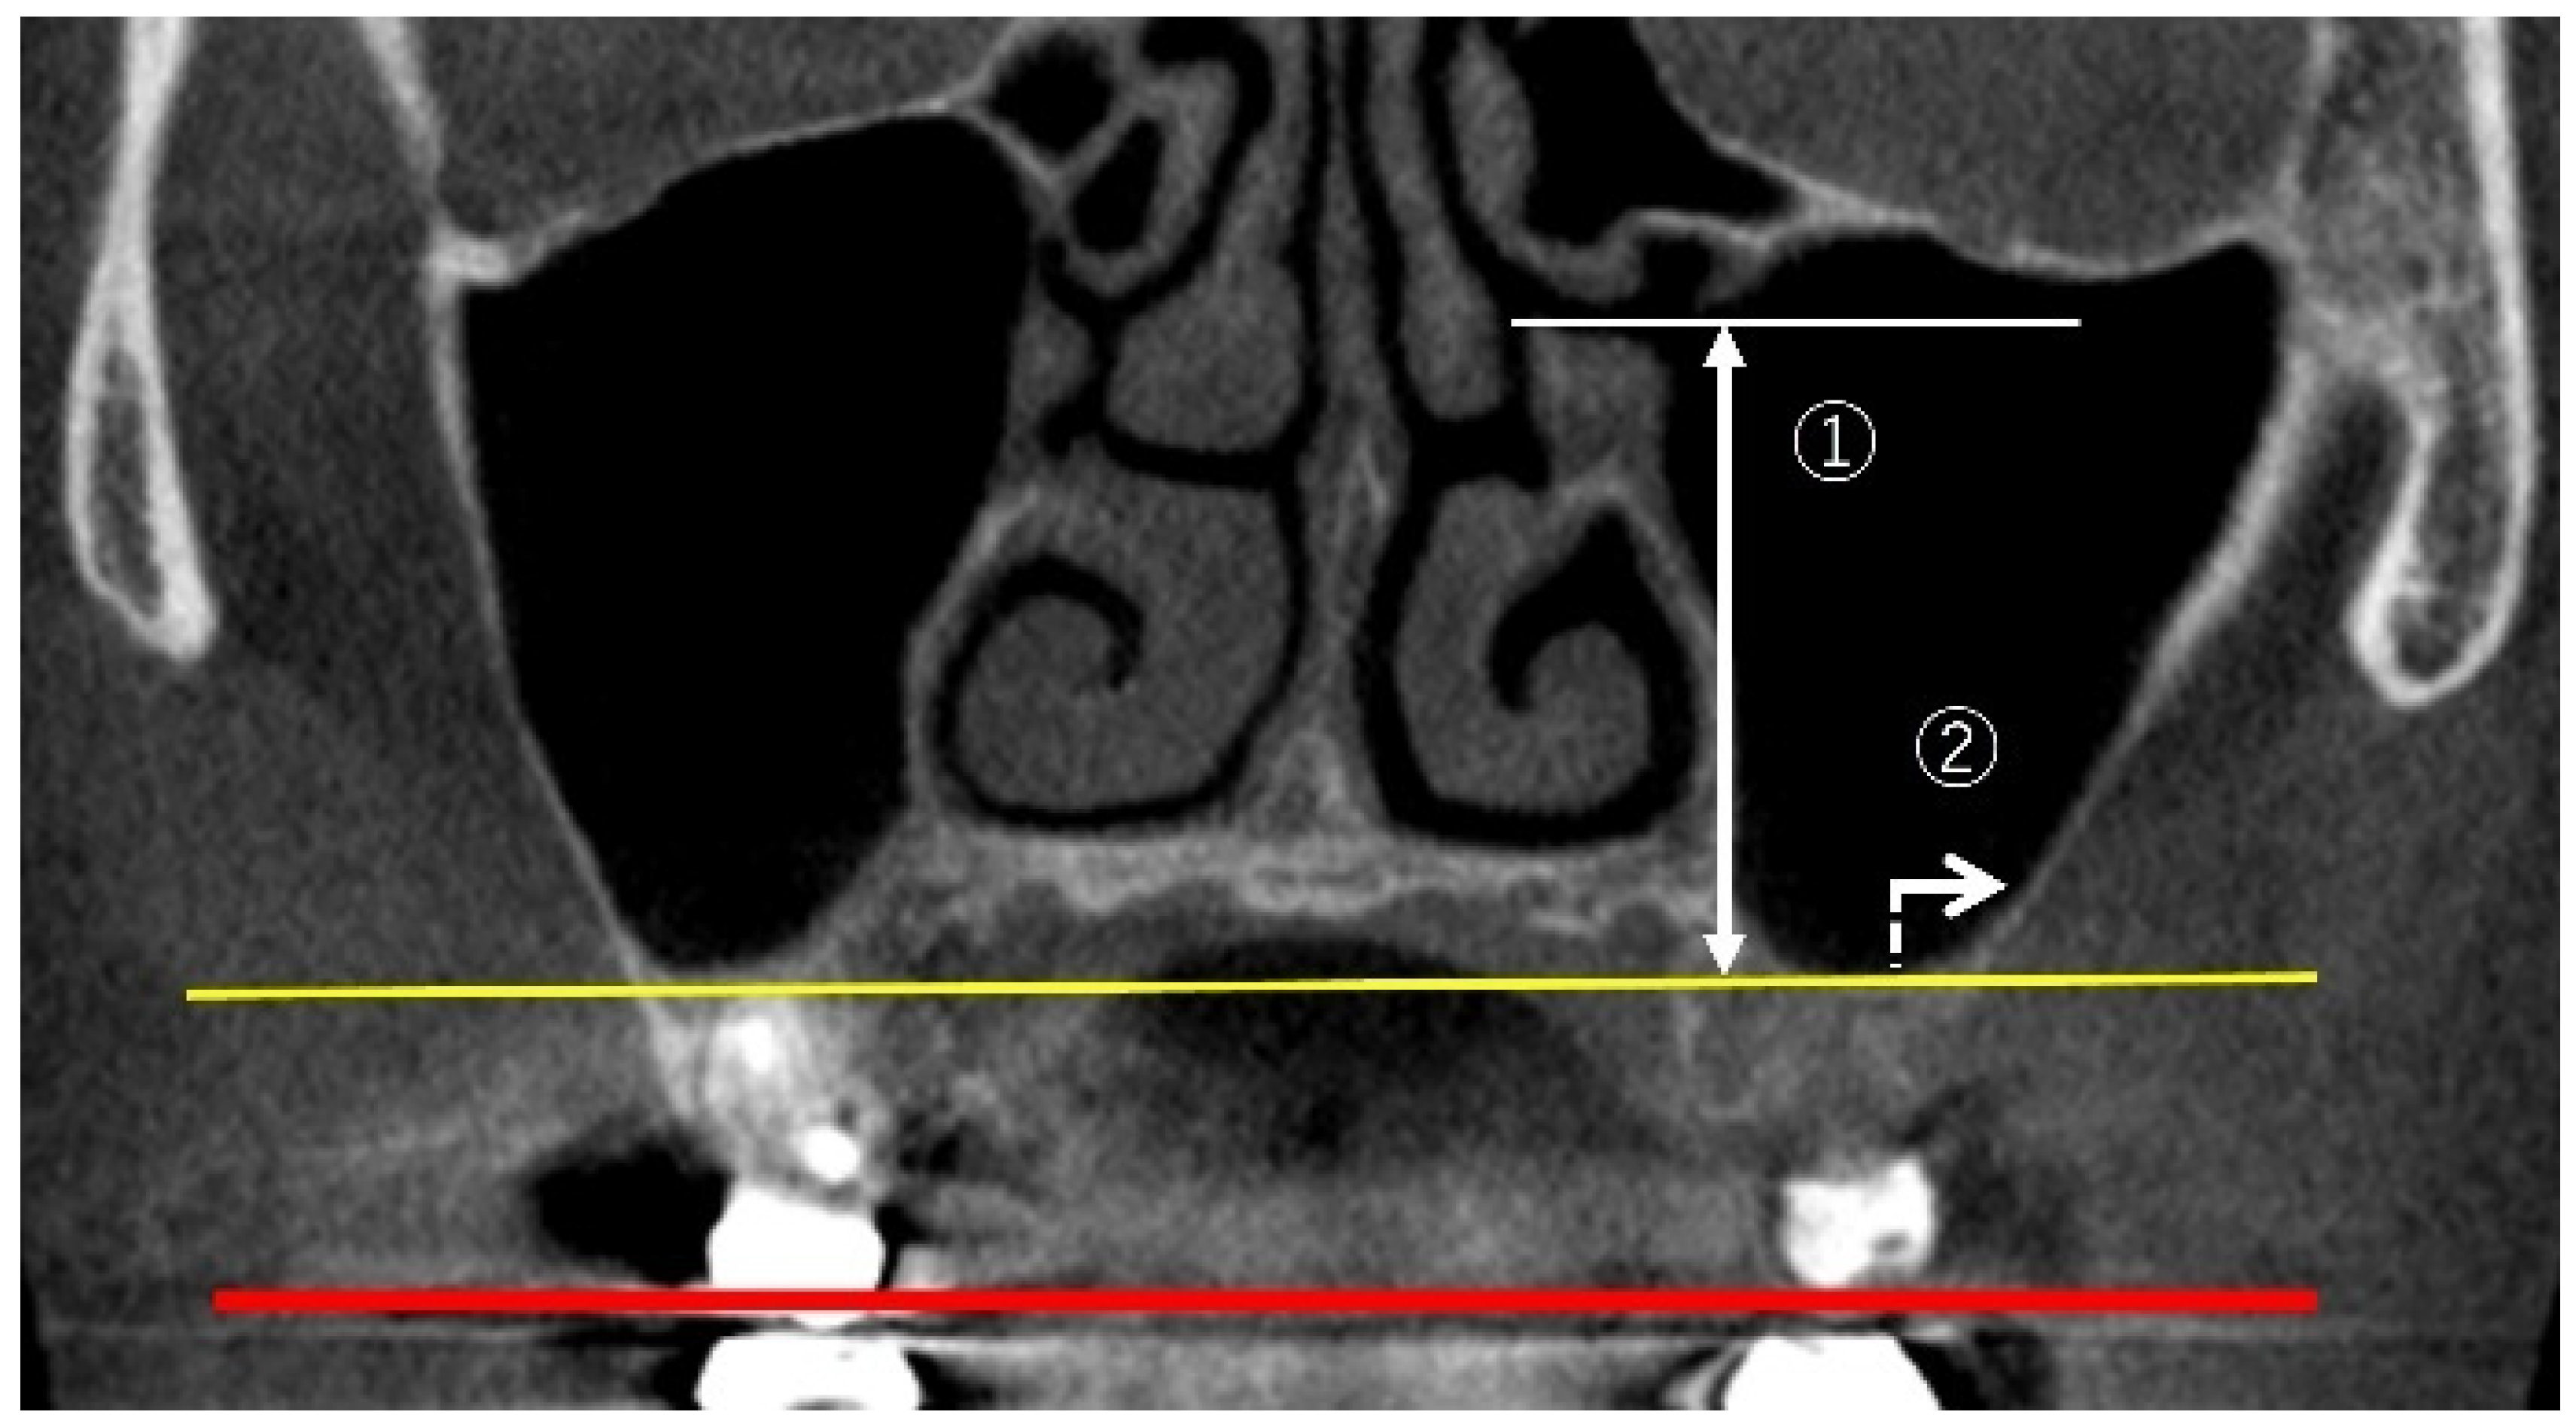

2.3.2. Measurement of PNR Angle and Maxillary Sinus Angle (MSA)

2.3.4. Linear Measurements of Maxillary Sinus Length